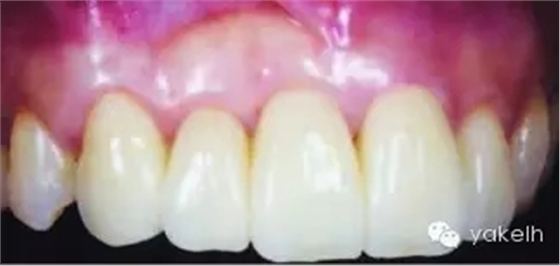

圖5.11 (a)患者休息放松狀態(tài)下的嘴唇——上下唇不能完全閉合。(b)右上尖牙和側(cè)切牙呈Ⅰ類牙齦退縮。(c)左上頜尖牙和側(cè)切牙呈Ⅱ類牙齦退縮。(d)先用圓形眼科刀片開始做溝內(nèi)切口。(e)使用探針在袋內(nèi)垂直探查貫通隧道,越過膜齦聯(lián)合。(f)使用探針在隧道內(nèi)橫向探查貫通,保留齦乳頭尖端附著于骨面。(g)從腭部取結締組織移植物,使用絲線牽引,將厚度和大小足夠的結締組織瓣插入隧道內(nèi)。(h)通過懸吊縫合將組織瓣冠向復位,穩(wěn)定結締組織瓣。(i)術后6個月,上頜右側(cè)觀。(j)上頜左側(cè)觀,可見牙齦厚度以及色澤的協(xié)調(diào)性均得到改善。(k)術后6個月正面觀,牙敏感癥狀消失。(l)術后1年的全口影像,顯示雙側(cè)的牙齦退縮均被完全覆蓋,牙齦邊緣增厚且穩(wěn)定,與釉牙骨質(zhì)界輪廓一致,也與左側(cè)中切牙釉質(zhì)缺損輪廓一致。(m)患者嶄新的笑容,可見側(cè)切牙及尖牙的齦緣無退縮。